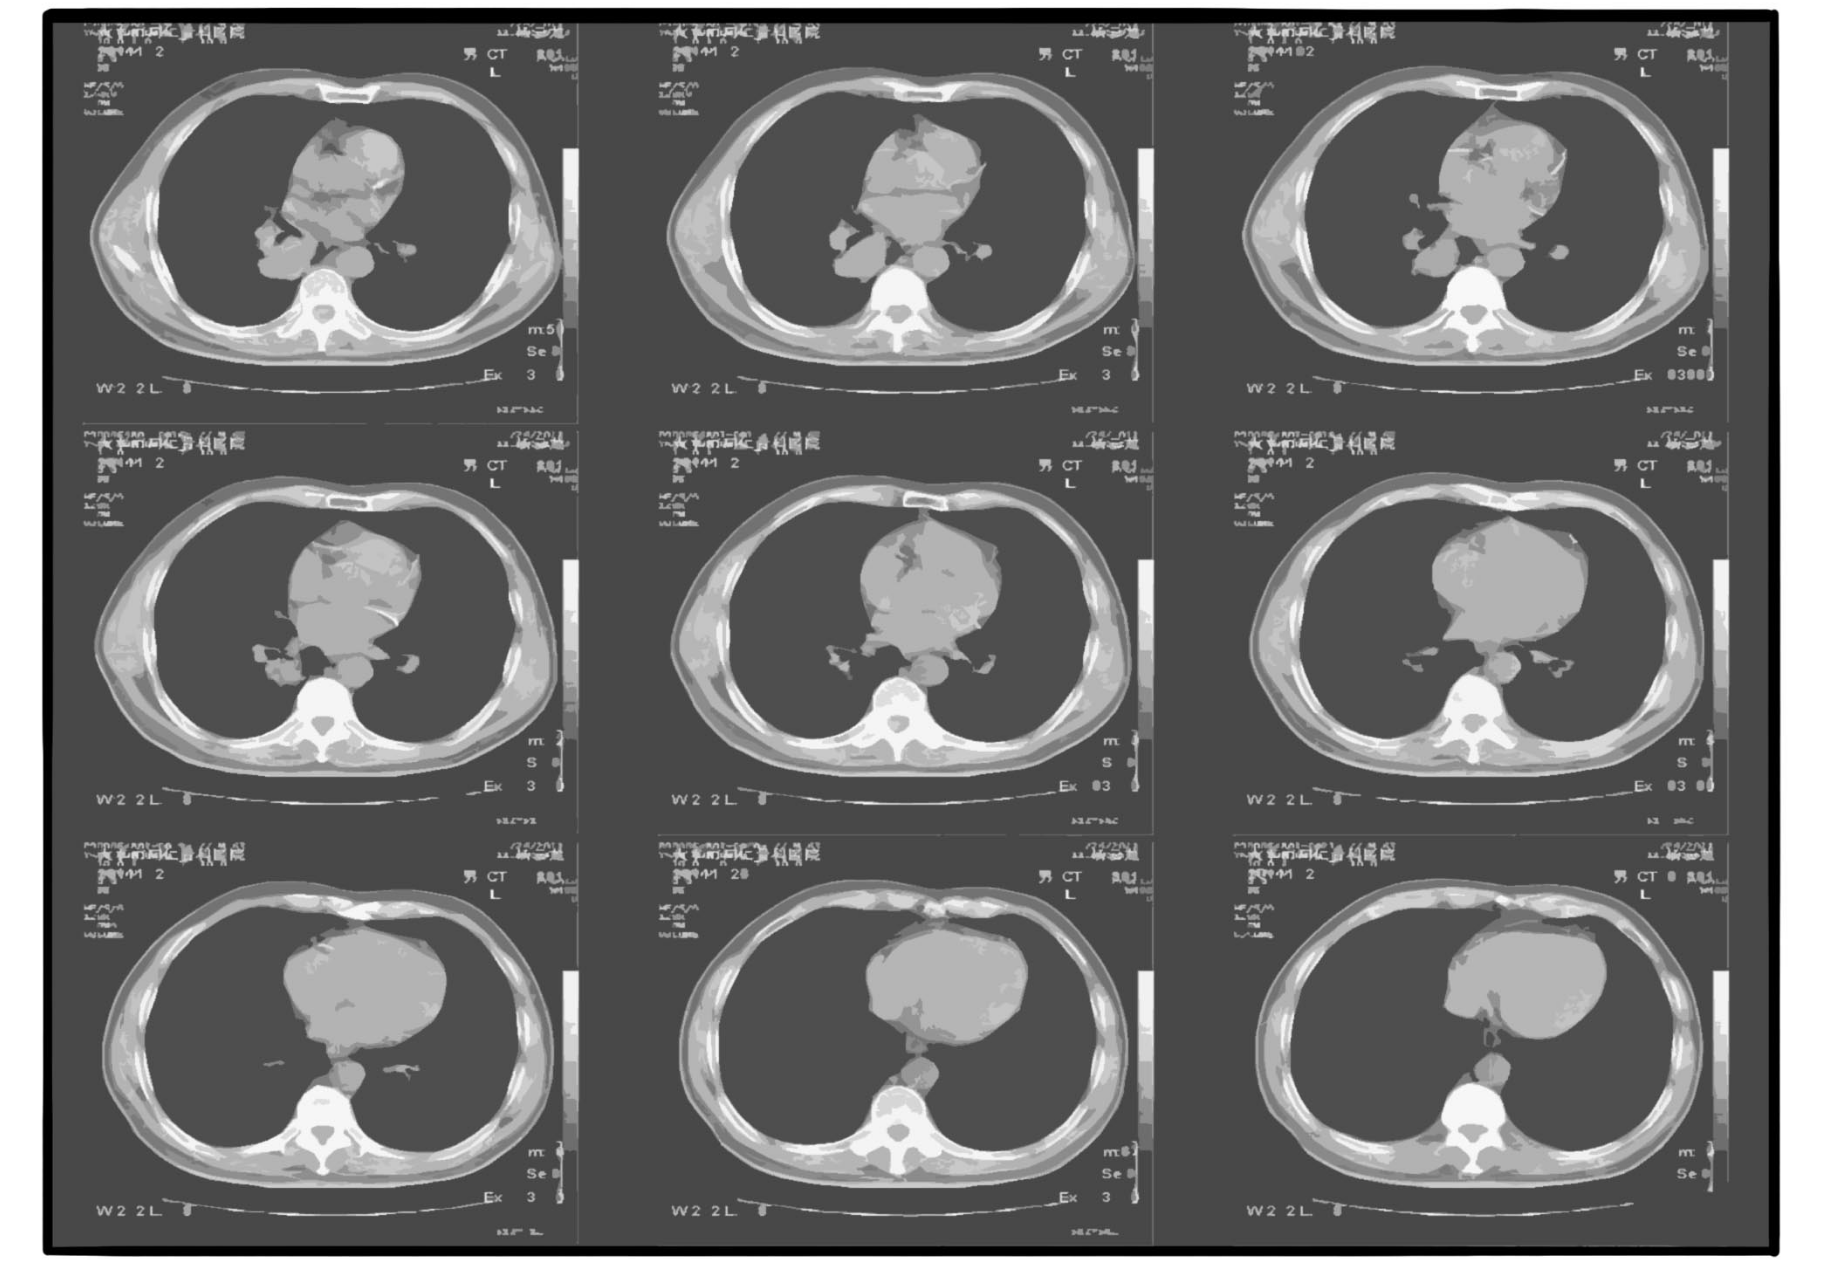

胸部CT检查范围广泛,涵盖了多个重要部位,主要包括肺部及胸膜、胸部骨性组织、纵隔及内部组织等,其是一种利用X线对胸部进行扫描,并将扫描结果转化为计算机图像,从而详细观察胸腔内部结构和病变情况的检查方法。

- 胸部CT能够检查纵隔内的肿瘤,如淋巴瘤、胸腺瘤、食管肿瘤、神经瘤等,以及纵隔内的其他病变情况。

- 胸部CT能够显示心脏的大小、形态和位置,判断是否存在心脏扩大、心包积液等心脏疾病。